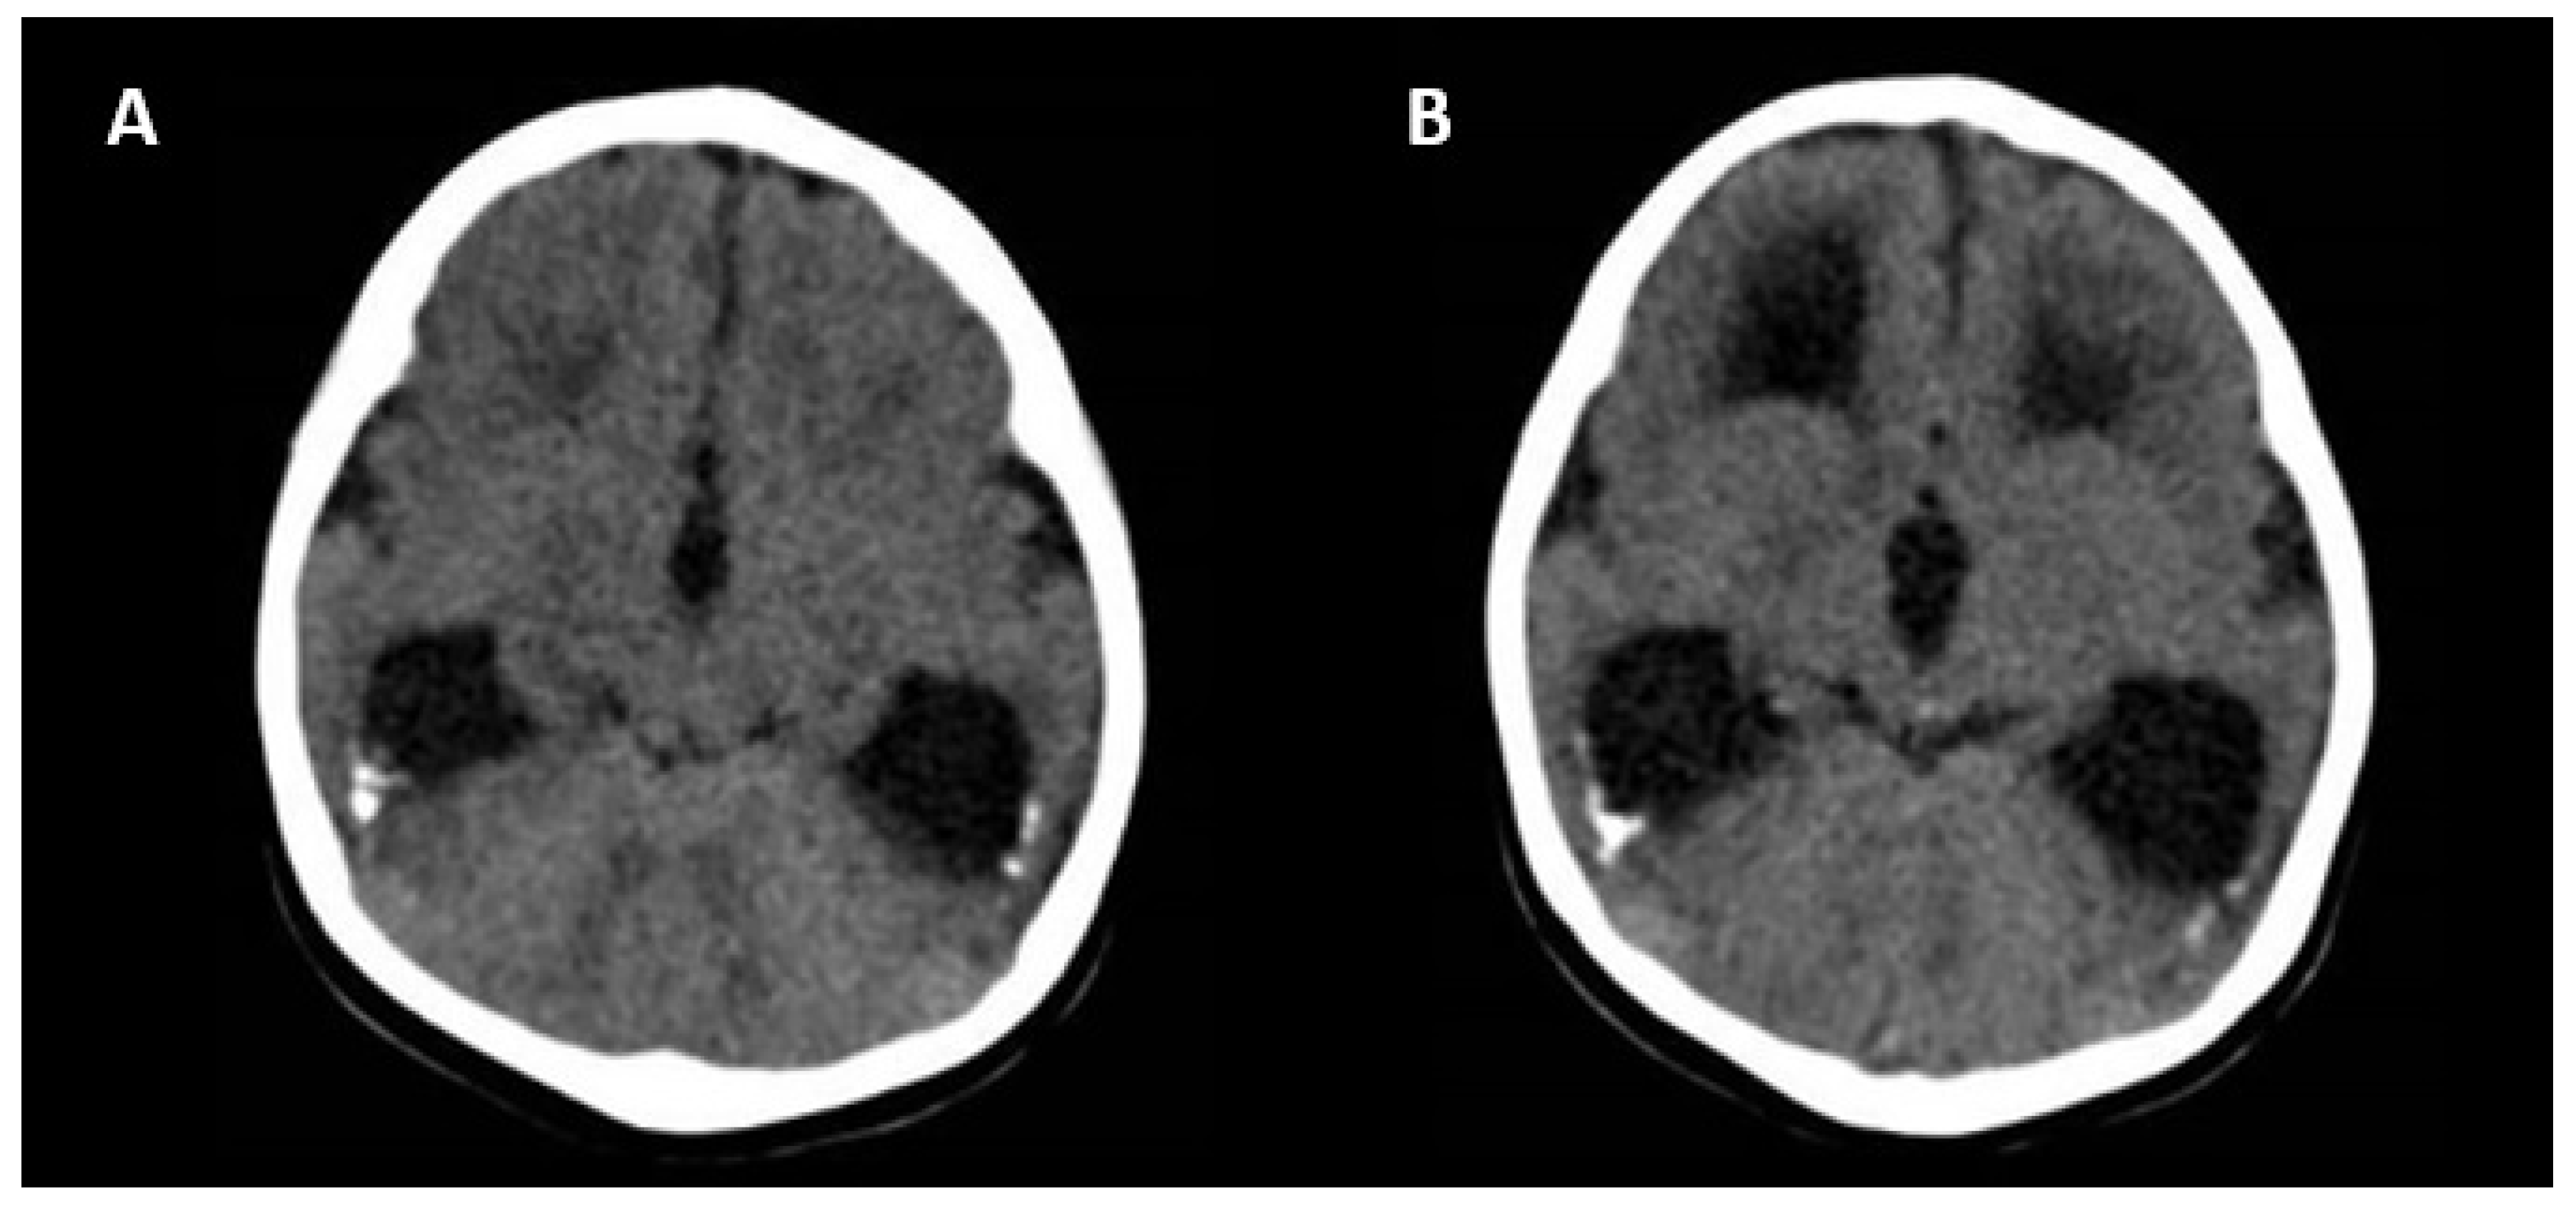

Ultrasonographic and Magnetic Resonance Imaging Findings

| CNS | |

| Moderate ventriculomegaly <15 mm Isolated cerebral calcification Isolated interventricular adhesion Vasculopathy/hyperechogenicity of lenticulostriate vessels |

|

| Severe CNS malformations | |

| Ventriculomegaly >15 mm Periventricular hyperechogenicity Hydrocephalus Microcephaly <3 SD Mega cisterna magna >10 mm Hypoplasia of vernix or cerebellum Porencephaly Lissencephaly Periventricular cysts Corpus callosum abnormality |

| Ultrasound or MRI | |